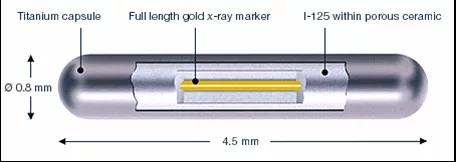

我“身高”4.5mm,“腰围”0.8 mm,肚子里装着吸附碘125粒子的银棒,外壳为0.05 mm厚的钛金属。我是“0-0-7”哦,可以24小时持续工作(释放能量)。另外我射线射程短(组织间有效射程直径只有1.7cm),大部分射线能量均被瘤体及组织所吸收,所以大家不用害怕我,无须特殊防护。